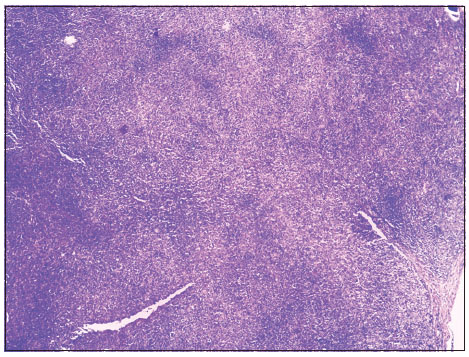

| Figure 1 Malignant adnexal skin tumor. Low‑power photomicrograph showing central cystic area with tumor cells. (H and E, ×40)